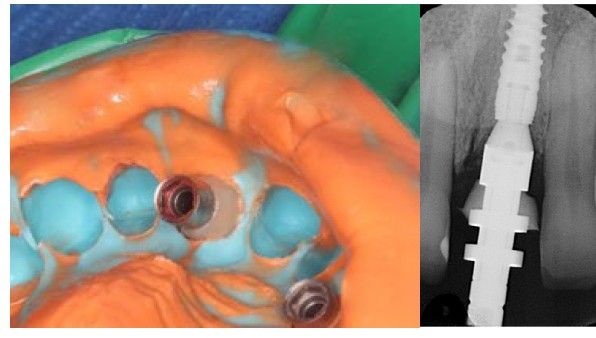

Como valoración preoperatoria, se realizaron registros fotográficos intraorales y extraorales, así como un escaneado intraoral de estudio. Como prueba complementaria, se efectuó un estudio mediante tomografía computarizada de haz cónico (CBCT) (Figura 1), que permitió analizar los factores determinantes para la ejecución de la técnica, tales como el biotipo óseo, la longitud radicular, el hueso residual disponible y la morfología de la cresta alveolar.

Una vez completado el análisis clínico y radiológico, se llevó a cabo un encerado diagnóstico digital con el objetivo de planificar previamente tanto el tipo de implante como el pilar protésico más adecuado para la restauración inmediata (Figura 2). A partir de dicho encerado, se confeccionó una corona provisional tipo “cáscara de huevo”, destinada a ser rebasada de manera directa en clínica tras la colocación del implante.

Posteriormente, siguiendo el protocolo de fresado recomendado por el fabricante, se colocó un implante de conexión interna (Klockner Vega Plus®3,6 × 12 mm) (Figura 4), alcanzándose un torque de inserción de 45 N/cm, lo que permitió la realización de una restauración provisional fija inmediata.

El implante se posicionó aproximadamente 4 mm subgingival en sentido vertical y manteniendo un gap vestibular superior a 2 mm en sentido horizontal (Figura 5). Dicho espacio fue rellenado con un xenoinjerto óseo de origen bovino (Bio-Oss®, Geistlich). A continuación, se realizó un injerto de tejido conectivo, obtenido de la tuberosidad maxilar, mediante una técnica de túnel en la zona vestibular, fijándolo con sutura reabsorbible incolora 5/0 (Monocryl Plus, Ethicon®) (Figura 6).